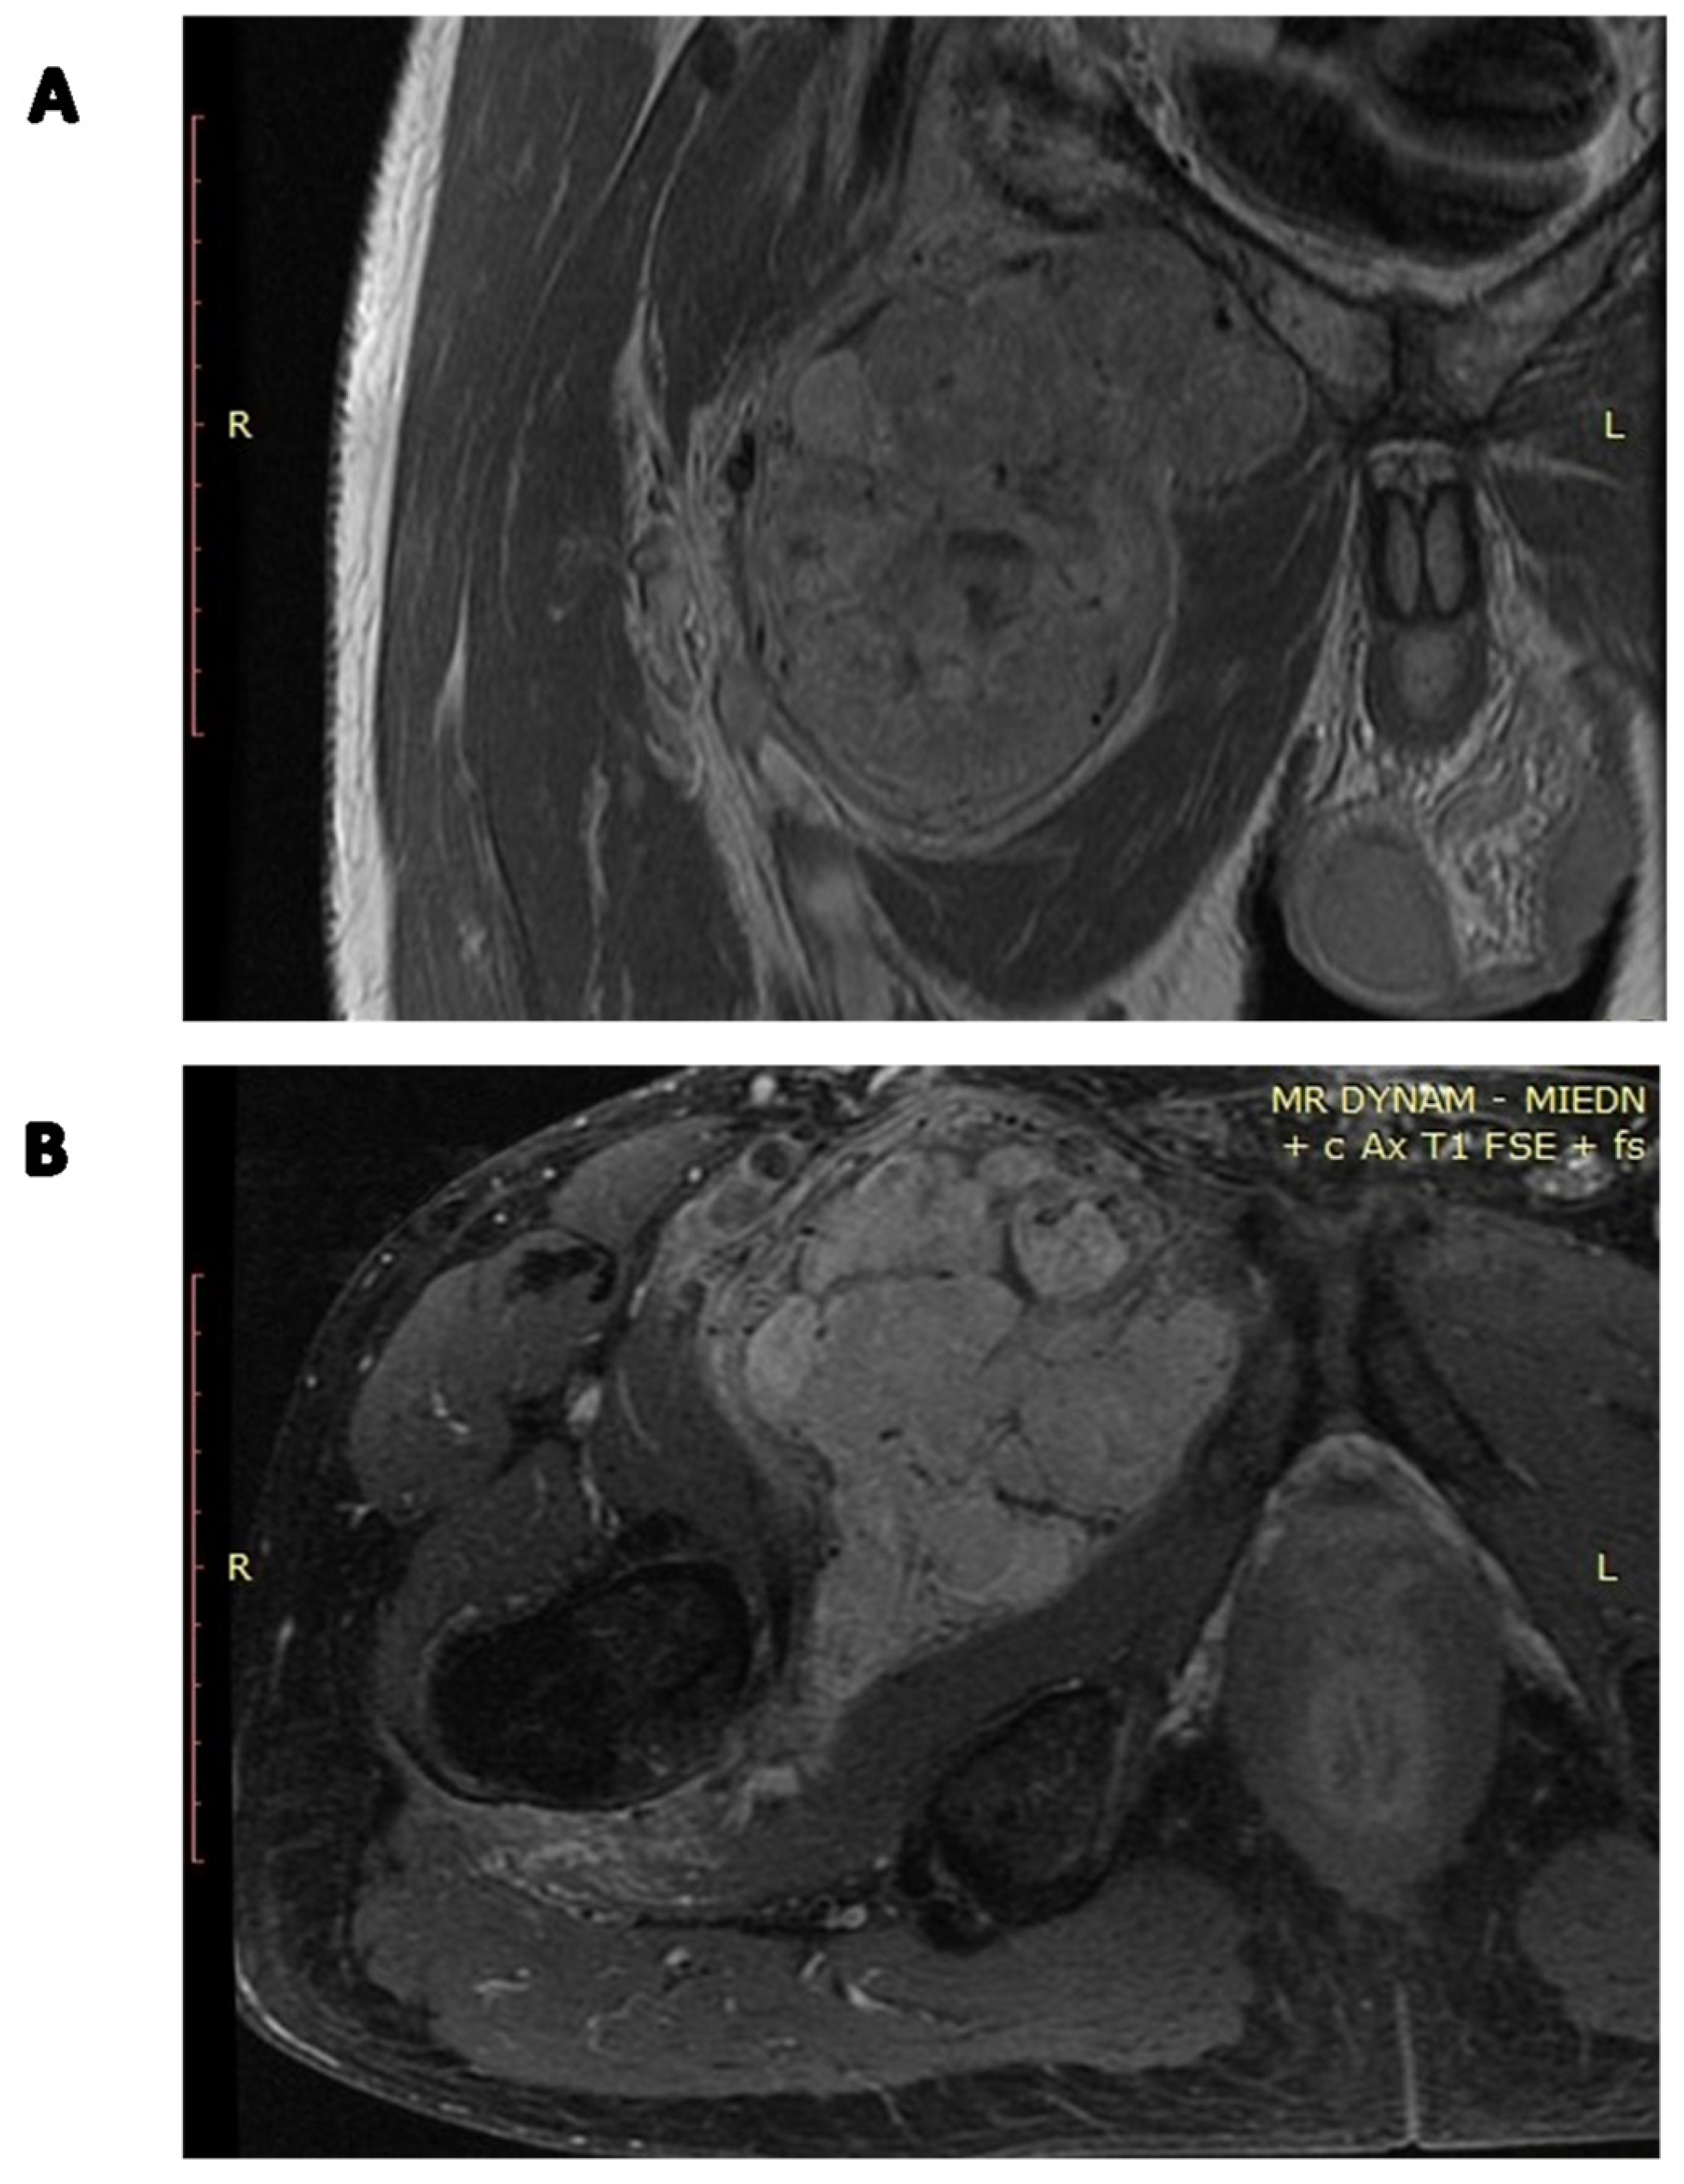

Figure 5.

Contrast-enhanced MRI image of a locally advanced abdominal SFT: (A) coronal image; (B) axial image.

Figure 6.

Contrast-enhanced MRI of the locally advanced left popliteal fossa SFT abutting popliteal vessels: (A) coronal image; (B) axial image.